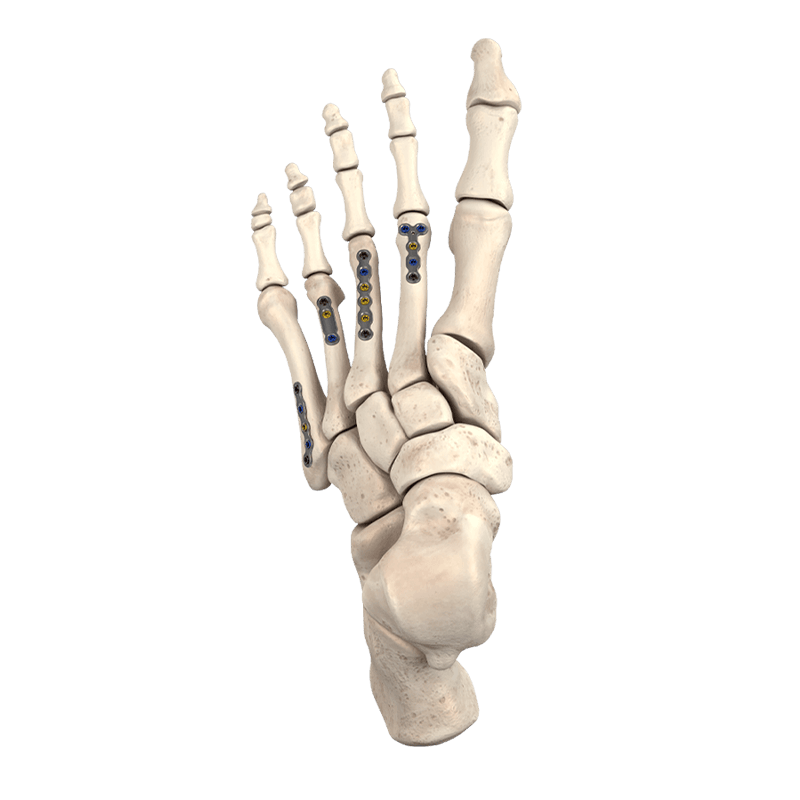

Plating Systems & Compression Hardware

Plating Systems & Compression Hardware

Plating systems and compression hardware for forefoot procedures.

Fixation Devices - Plating Systems

CoLink® Mini Dynamic Compression Plating System

Comprehensive plating system designed to address a variety of fractures and fusions

CoLink® Mfx Midfoot Plating System

Designed to address fractures, fusions, and osteotomies of the midfoot

CoLink® NX MTP Compression Plating System

Featuring an elliptical slot with progressive depth that aids mechanical compression

CoLink® XP Plating System

Achieve dynamic transverse compression via transverse lag screw

5MS® Plating System

Low-profile plate system provides ease of plating, specifically for proximal 5th metatarsal fractures or Jones Fracture indications, IM screw nonunions, curved 5th metatarsals, and sclerotic nonunions.